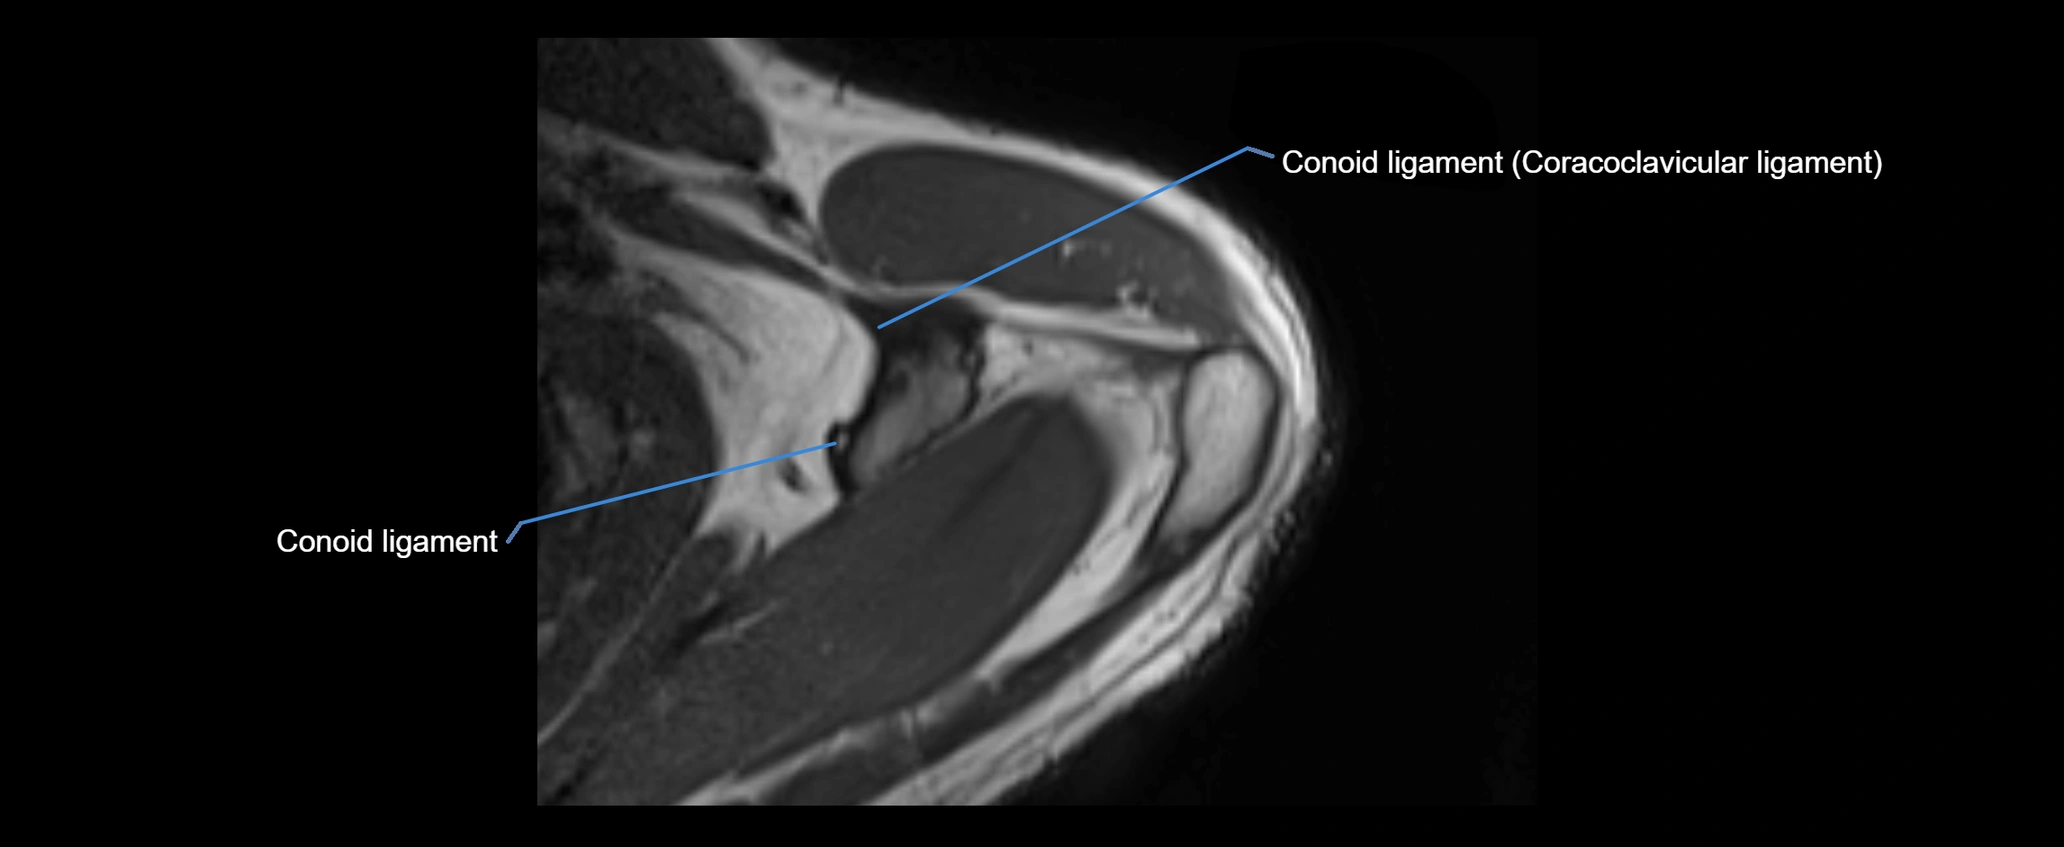

MRI Appearance

• T1-weighted images:

• Normal ligament: Low signal (dark linear band) spanning acromion to clavicle.

• Surrounding fat planes: Bright, delineating the ligament clearly.

• Marrow of clavicle and acromion: Bright due to fatty content.

• Tears: Discontinuity or irregular thickening with intermediate-to-bright signal.

• Chronic injury: Thinning, fraying, or irregular low-signal fibers with adjacent scarring.

• T2-weighted images:

• Normal ligament: Low signal, homogeneous.

• Partial tear or sprain: Focal hyperintensity or thickening.

• Complete tear: Discontinuity with fluid-bright gap between clavicle and acromion.

• Associated edema: Bright signal in distal clavicle or acromion marrow.

• STIR:

• Normal ligament: Dark linear band.

• Injury or inflammation: Bright hyperintense signal in and around ligament fibers.

• Highlights periligamentous soft-tissue edema, especially in acute trauma.

• Proton Density Fat-Saturated (PD FS):

• Normal ligament: Low signal, uniform thickness.

• Partial tear or sprain: Bright signal or contour irregularity.

• Complete tear: Clear discontinuity with bright signal gap and joint effusion.

• Excellent for assessing joint capsule, coracoclavicular ligaments, and periarticular edema.

MRI images

image